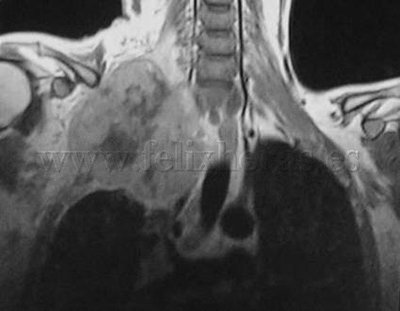

Cáncer de pulmón